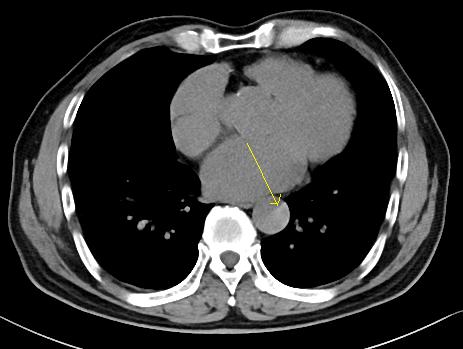

下图的胸部CT平扫,有什么大问题?

图4

仔细一看,主动脉里面有线样高密度阴影!这个要高度警惕主动脉夹层!

图5